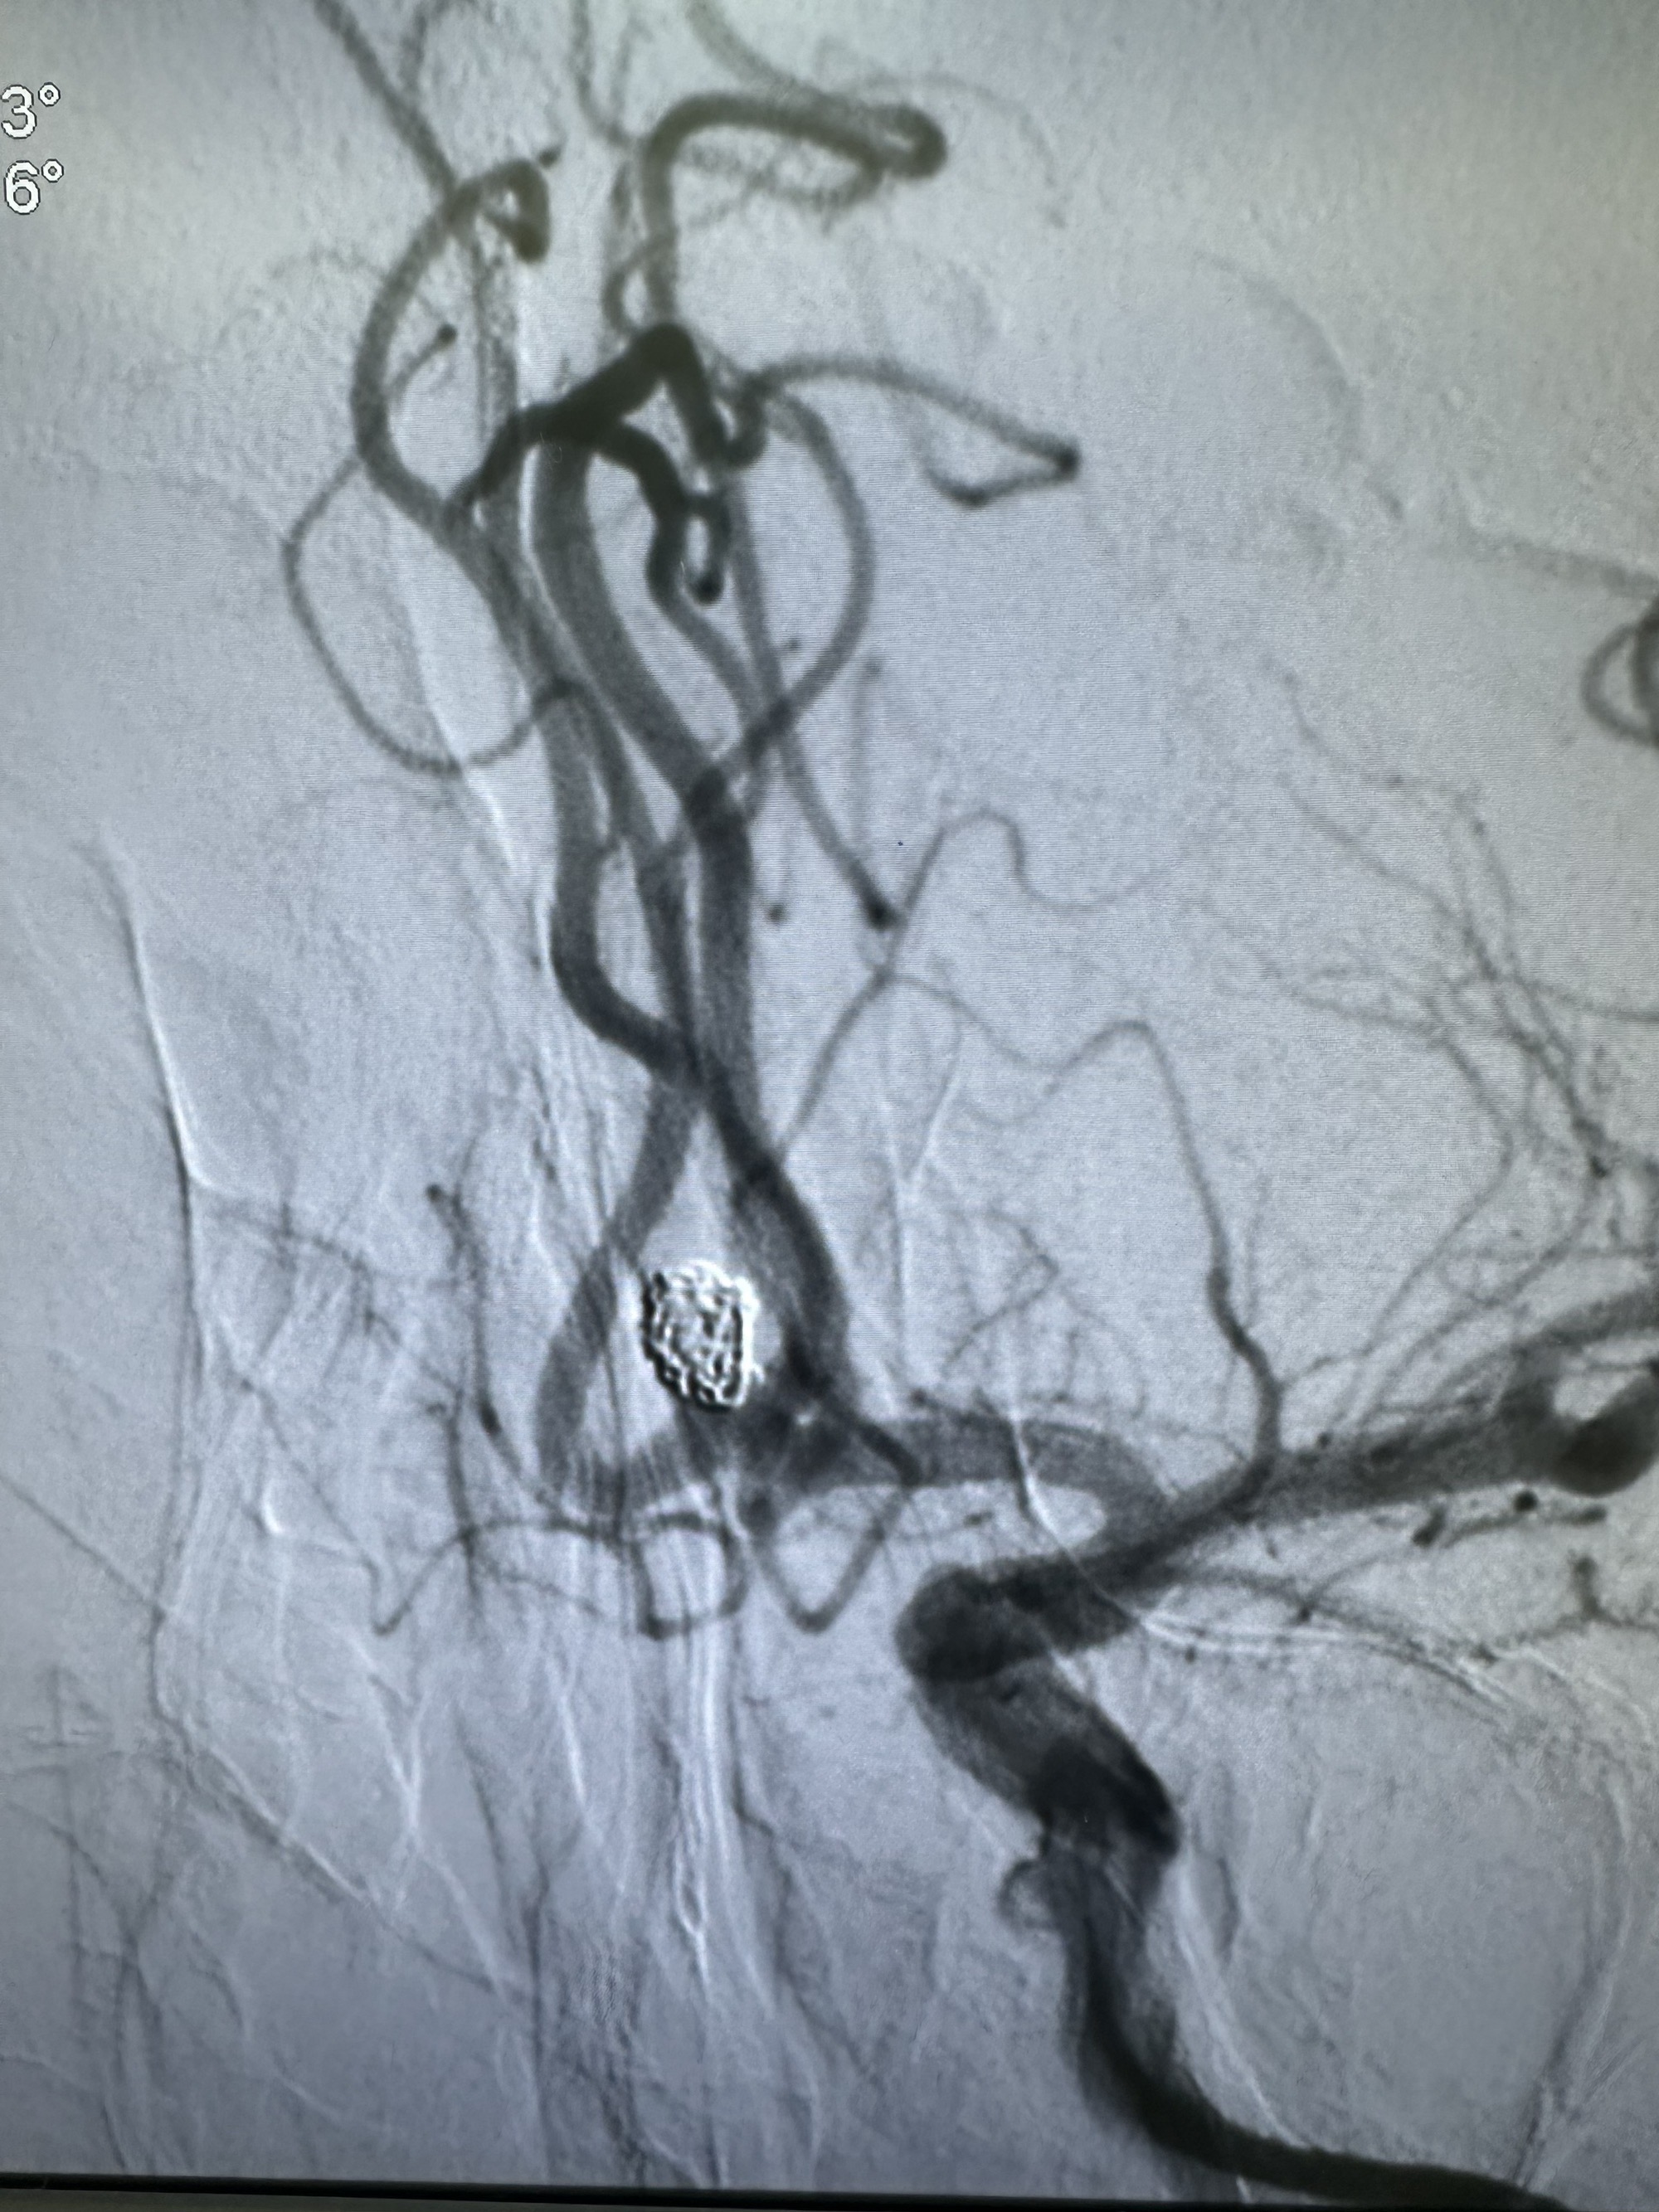

正位